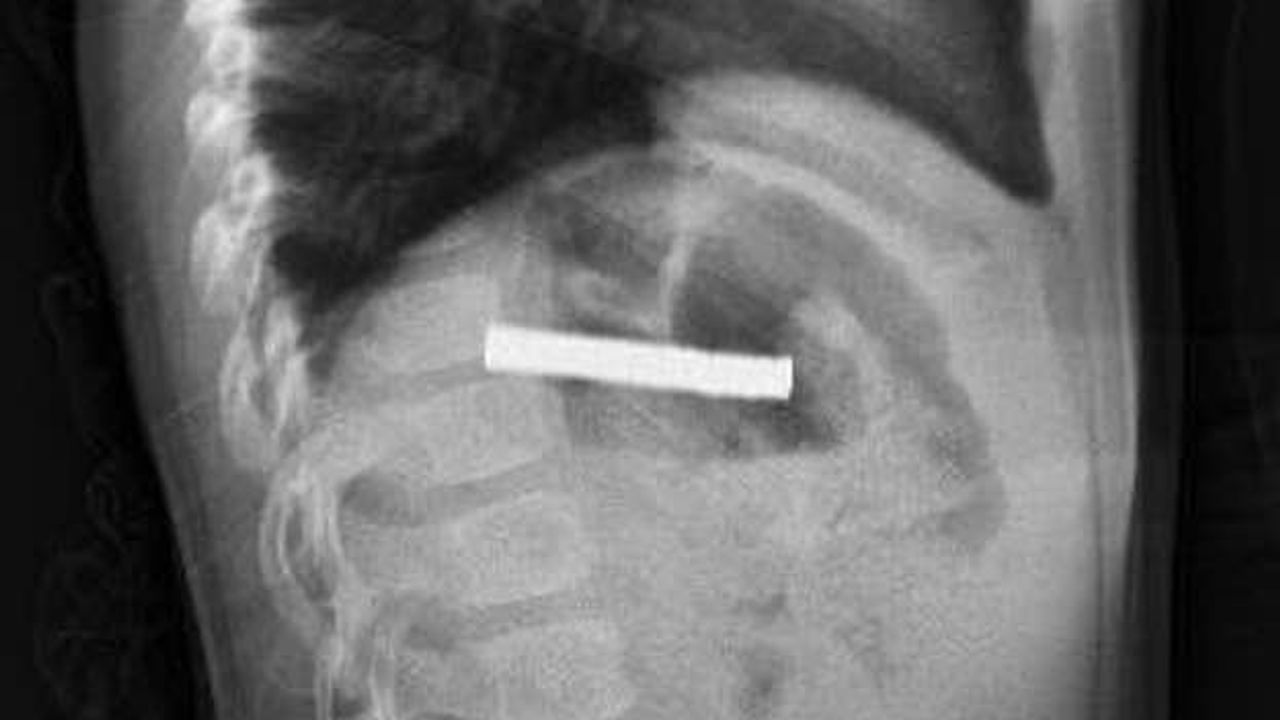

Erzurum’da 3 yaşındaki bir çocuk, evde bulduğu 19 adet küçük mıknatısı yuttu. Ailenin durumu fark etmesi üzerine çocuk ilk olarak Erzurum’da bir hastaneye götürüldü. Yapılan değerlendirme sonrası hasta, ileri tetkik ve tedavi amacıyla Elazığ’a sevk edildi.

Fırat Üniversitesi Hastanesi’nde gerçekleştirilen müdahale ile çocuk, sağlık ekipleri tarafından tedavi altına alındı. Fırat Üniversitesi Tıp Fakültesi Çocuk Gastroenteroloji Hepatoloji ve Beslenme Bilim Dalı Başkanı Prof. Dr. Yaşar Doğan tarafından gerçekleştirilen endoskopik işlemle, çocuğun yemek borusuna yapışan 19 mıknatıs çıkarıldı.